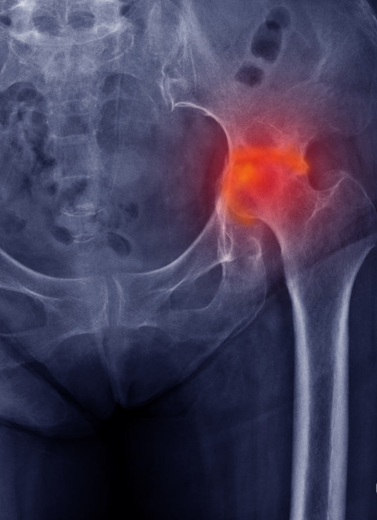

DAA Total Hip Replacement

Avascular Necrosis (AVN)

No limb length discrepancy in DAA hip replacement